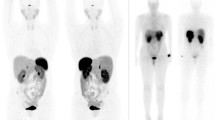

As the natural GLP-1 ligand is rapidly degraded by dipeptidyl-peptidase-4 (DPP4) [73], the DPP4-resistant GLP-1 analogue exendin-4 was developed. Using the radioisotope Indium-111, exendin-4 was then coupled via the chelator DTPA, leading to the radiotracer 111In-DTPA-exendin-4 [74, 75]. The initial promising proof-of-principle data [75, 76] were later confirmed in a multicentre study [77]. In this study of 30 insulinoma patients, 111In-DTPA-exendin-4-SPECT/CT showed superior diagnostic sensitivity to conventional MRI. The final break-through was achieved, when exendin-4 was coupled to 68Ga-DOTA allowing for PET imaging [78]. In a prospective study evaluating 52 patients with suspected benign insulinoma, 68Ga-DOTA-exendin-4 PET/CT showed a higher diagnostic accuracy of 94% compared to 68% with 111In-DOTA-exendin-4 SPECT/CT and standardized 3-Tesla-MRI (Fig. 2) [79•]. Furthermore, 68Ga-DOTA-exendin-4 PET/CT also proved useful in the evaluation of the usually multiple pancreatic lesions in patients with multiple endocrine neoplasms type 1 (MEN-1) patients [80].

Targeting of GLP-1R with 68Ga-DOTA-exendin-4 PET/CT. Patient with biochemically confirmed endogenous hyperinsulinemic hypoglycemia. CT and MRI were negative. Coronal (A) and transaxial (B) PET/CT showed focal 68Ga-DOTA-exendin-4 uptake in the body of the pancreas (white arrows) consistent with a benign insulinoma. Coronal (C) and transaxial (D) T1-weighted MRI showed a slightly hypointense signal at the same location (white arrows) and was only retrospectively interpreted as a suspicious lesion. Histology confirmed an insulinoma in the pancreatic body

With its additional advantage of having a shorter investigation time with a lower radiation burden, 68Ga-DOTA-exendin-4 PET/CT was proposed the diagnostic method of choice for suspected insulinoma negative on conventional imaging, thereby avoiding the cumbersome selective intra-arterial calcium stimulation and venous sampling test. As DOTA-exendin-4 can induce hypoglycemia, a concomitant glucose-infusion is recommended. Transient nausea and vomiting were also reported shortly after injection of the tracer.